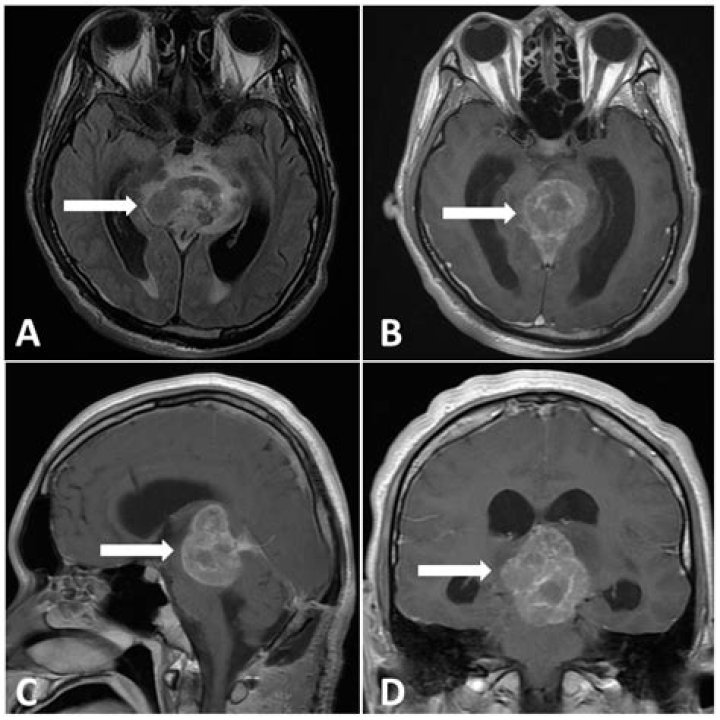

Pineal cysts are best seen on brain magnetic resonance imaging (MRI). This type of brain imaging is typically reviewed by a specialist, such as a neuroradiologist, who is experienced in evaluating brain cysts and tumors.

Pineal cyst.

This happens on the pineal gland in the middle of the brain. This type of cyst often only shows up during imaging scans done for another reason. Pineal cysts seldom cause problems. If they do grow large, they can sometimes affect vision.

Pineal cysts are common findings in neuroimaging studies. The cysts are more frequent in women in their third decade of life. Pineal cysts can be symptomatic, headache is the most common symptom.

Should pineal cysts be monitored?

Conclusions: Incidental pineal cysts typically show a benign course. In the adult population, they do not require long-term neurosurgical follow-up, because pineal cysts tend to remain a stable size. In asymptomatic patients, we recommend a single follow-up MRI scan at 12 months to confirm diagnosis.